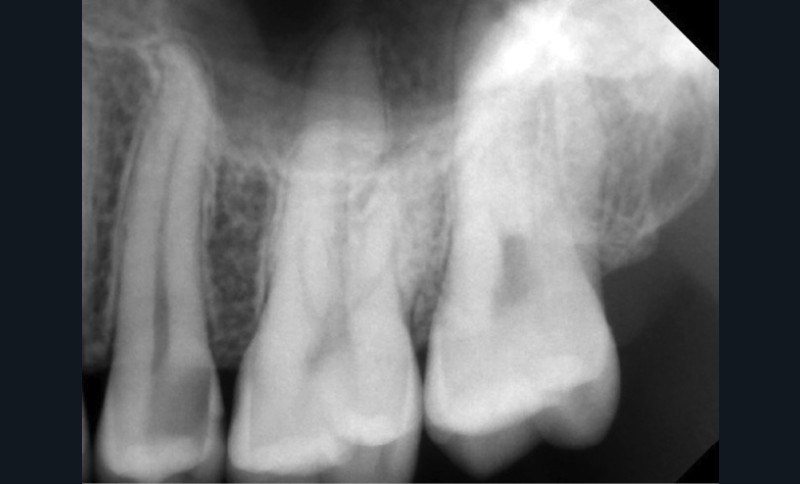

Si l’étude de Peters [18] nous montre que l’instrumentation laisse 35 % du volume canalaire non instrumenté, Ricucci et Siqueira montrent que la préparation physico-chimique n’élimine que partiellement les tissus nécrotiques à l’entrée des canaux latéraux, des isthmes et des ramifications apicales, en laissant des tissus enflammés et infectés, en association avec des lésions apicales [29] (fig. 4 et 5).

Fig. 4 – Coupe d’une racine mésiale de molaire mandibulaire avec deux canaux traités. Coupe à 3 mm de l’apex, coloration Brown et Brenn, technique modifiée par Taylor. Ces images montrent un isthme étroit avec une infection bactérienne, ce qui prouve l’importance de désinfecter et d’inclure l’isthme dans les traitements conventionnels et dans les rétropréparations apicales en chirurgie endodontique.